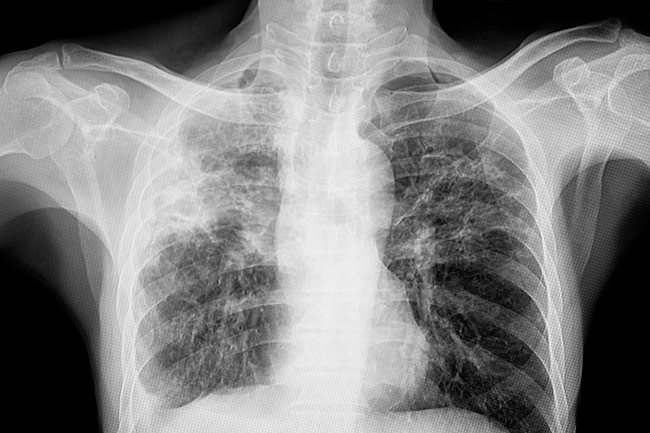

Diagnosis fibrosis paru non-idiopatik ditekankan pada mengidentifikasi kondisi medis yang mendasari timbulnya fibrosis paru. Gejala yang dapat timbul antara lain sesak, batuk, dan napas berbunyi. Pemeriksaan penunjang radiologi akan menunjukkan adanya fibrosis pada parenkim paru. Pemeriksaan penunjang lain, seperti penanda penyakit autoimun atau spirometri, mungkin dapat bermanfaat sesuai skenario klinis masing-masing pasien.